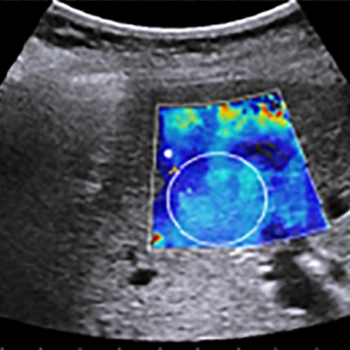

এই কারণেই তৈরি হয়েছে একটি বিশেষ পদ্ধতি যার নাম Shear Wave Elastography (SWE)। এই পদ্ধতিতে একধরনের ক্ষুদ্র কম্পন বা shear wave শরীরের ভেতরে পাঠানো হয়। এই তরঙ্গ পাশের দিকে ছড়িয়ে পড়ে এবং তার গতি (shear wave speed) থেকে বোঝা যায় টিস্যুটি কতটা শক্ত বা নরম। তরঙ্গ যত দ্রুত যাবে, টিস্যু তত শক্ত—এটাই মূল ধারণা।

তাই SWE হলো এমন এক non-invasive (অর্থাৎ অস্ত্রোপচার ছাড়া), real-time (অর্থাৎ সঙ্গে সঙ্গে দেখা যায়) এবং সাশ্রয়ী প্রযুক্তি, যা অনেক উন্নত দেশে চিকিৎসকদের নিয়মিত ব্যবহার্য।

এটি তৈরি করে একদম পরিষ্কার stiffness map, যা চিকিৎসকদের শরীরের ভেতরের কঠিন ও নরম অংশগুলো সহজে আলাদা করতে সাহায্য করে।